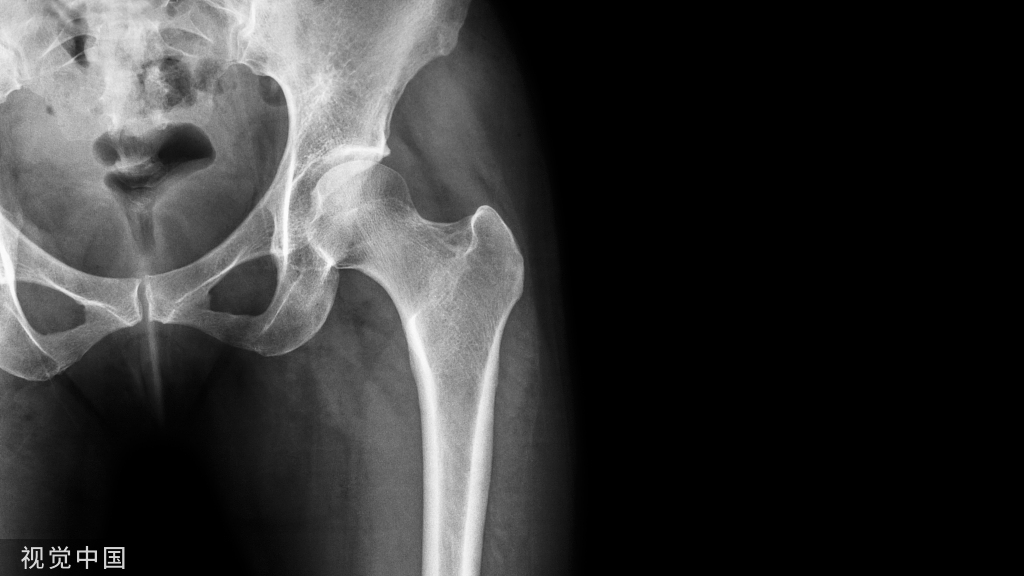

要特别强调的是,开口一定要充分。否则,很容易造成插钉时骨折的移位。但实际上,由于操作空间的限制以及该处皮质内紧外松的特点,临床上经常会发现扩髓时内侧比较坚硬的皮质,经常会阻挡并且推顶扩髓钻向更松软的大粗隆侧移位,造成进针点外移这种现象。

每个医生都有自己的小窍门来克服这种现象:

- 有的医生可以矫枉过正,开口稍微內移一点

- 有的医生利用手头各种各样的工具,比如说拉钩、剥离子顶着扩髓钻,施加一个向内的分力,以减少外侧皮质的干扰

- 也有的医生用一块小钢板保护外侧壁,以保证其不受干扰

- 或者用导针向上弧形折顶的方法,利用导针本身的弹性以达到对外侧皮质的保护

示意图:开口及扩髓利用器械辅助避免损伤外侧壁